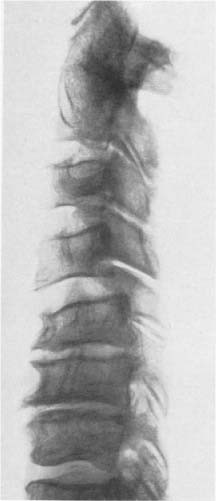

Seitliches Röntgenbild der Halswirbelsäule in Abb. 66. Infolge der Ausbiegung der Processus uncinati können sich die Wirbelkörper bis zur Berührung nähern. Sie sind wie Quader zu einer Säule übereinander gestellt. Die Zeichen der Osteochondrose und die ventralen Randzacken sind ausgeprägt. In den unteren Segmenten besteht eine Kyphose. (74jähriger Mann)